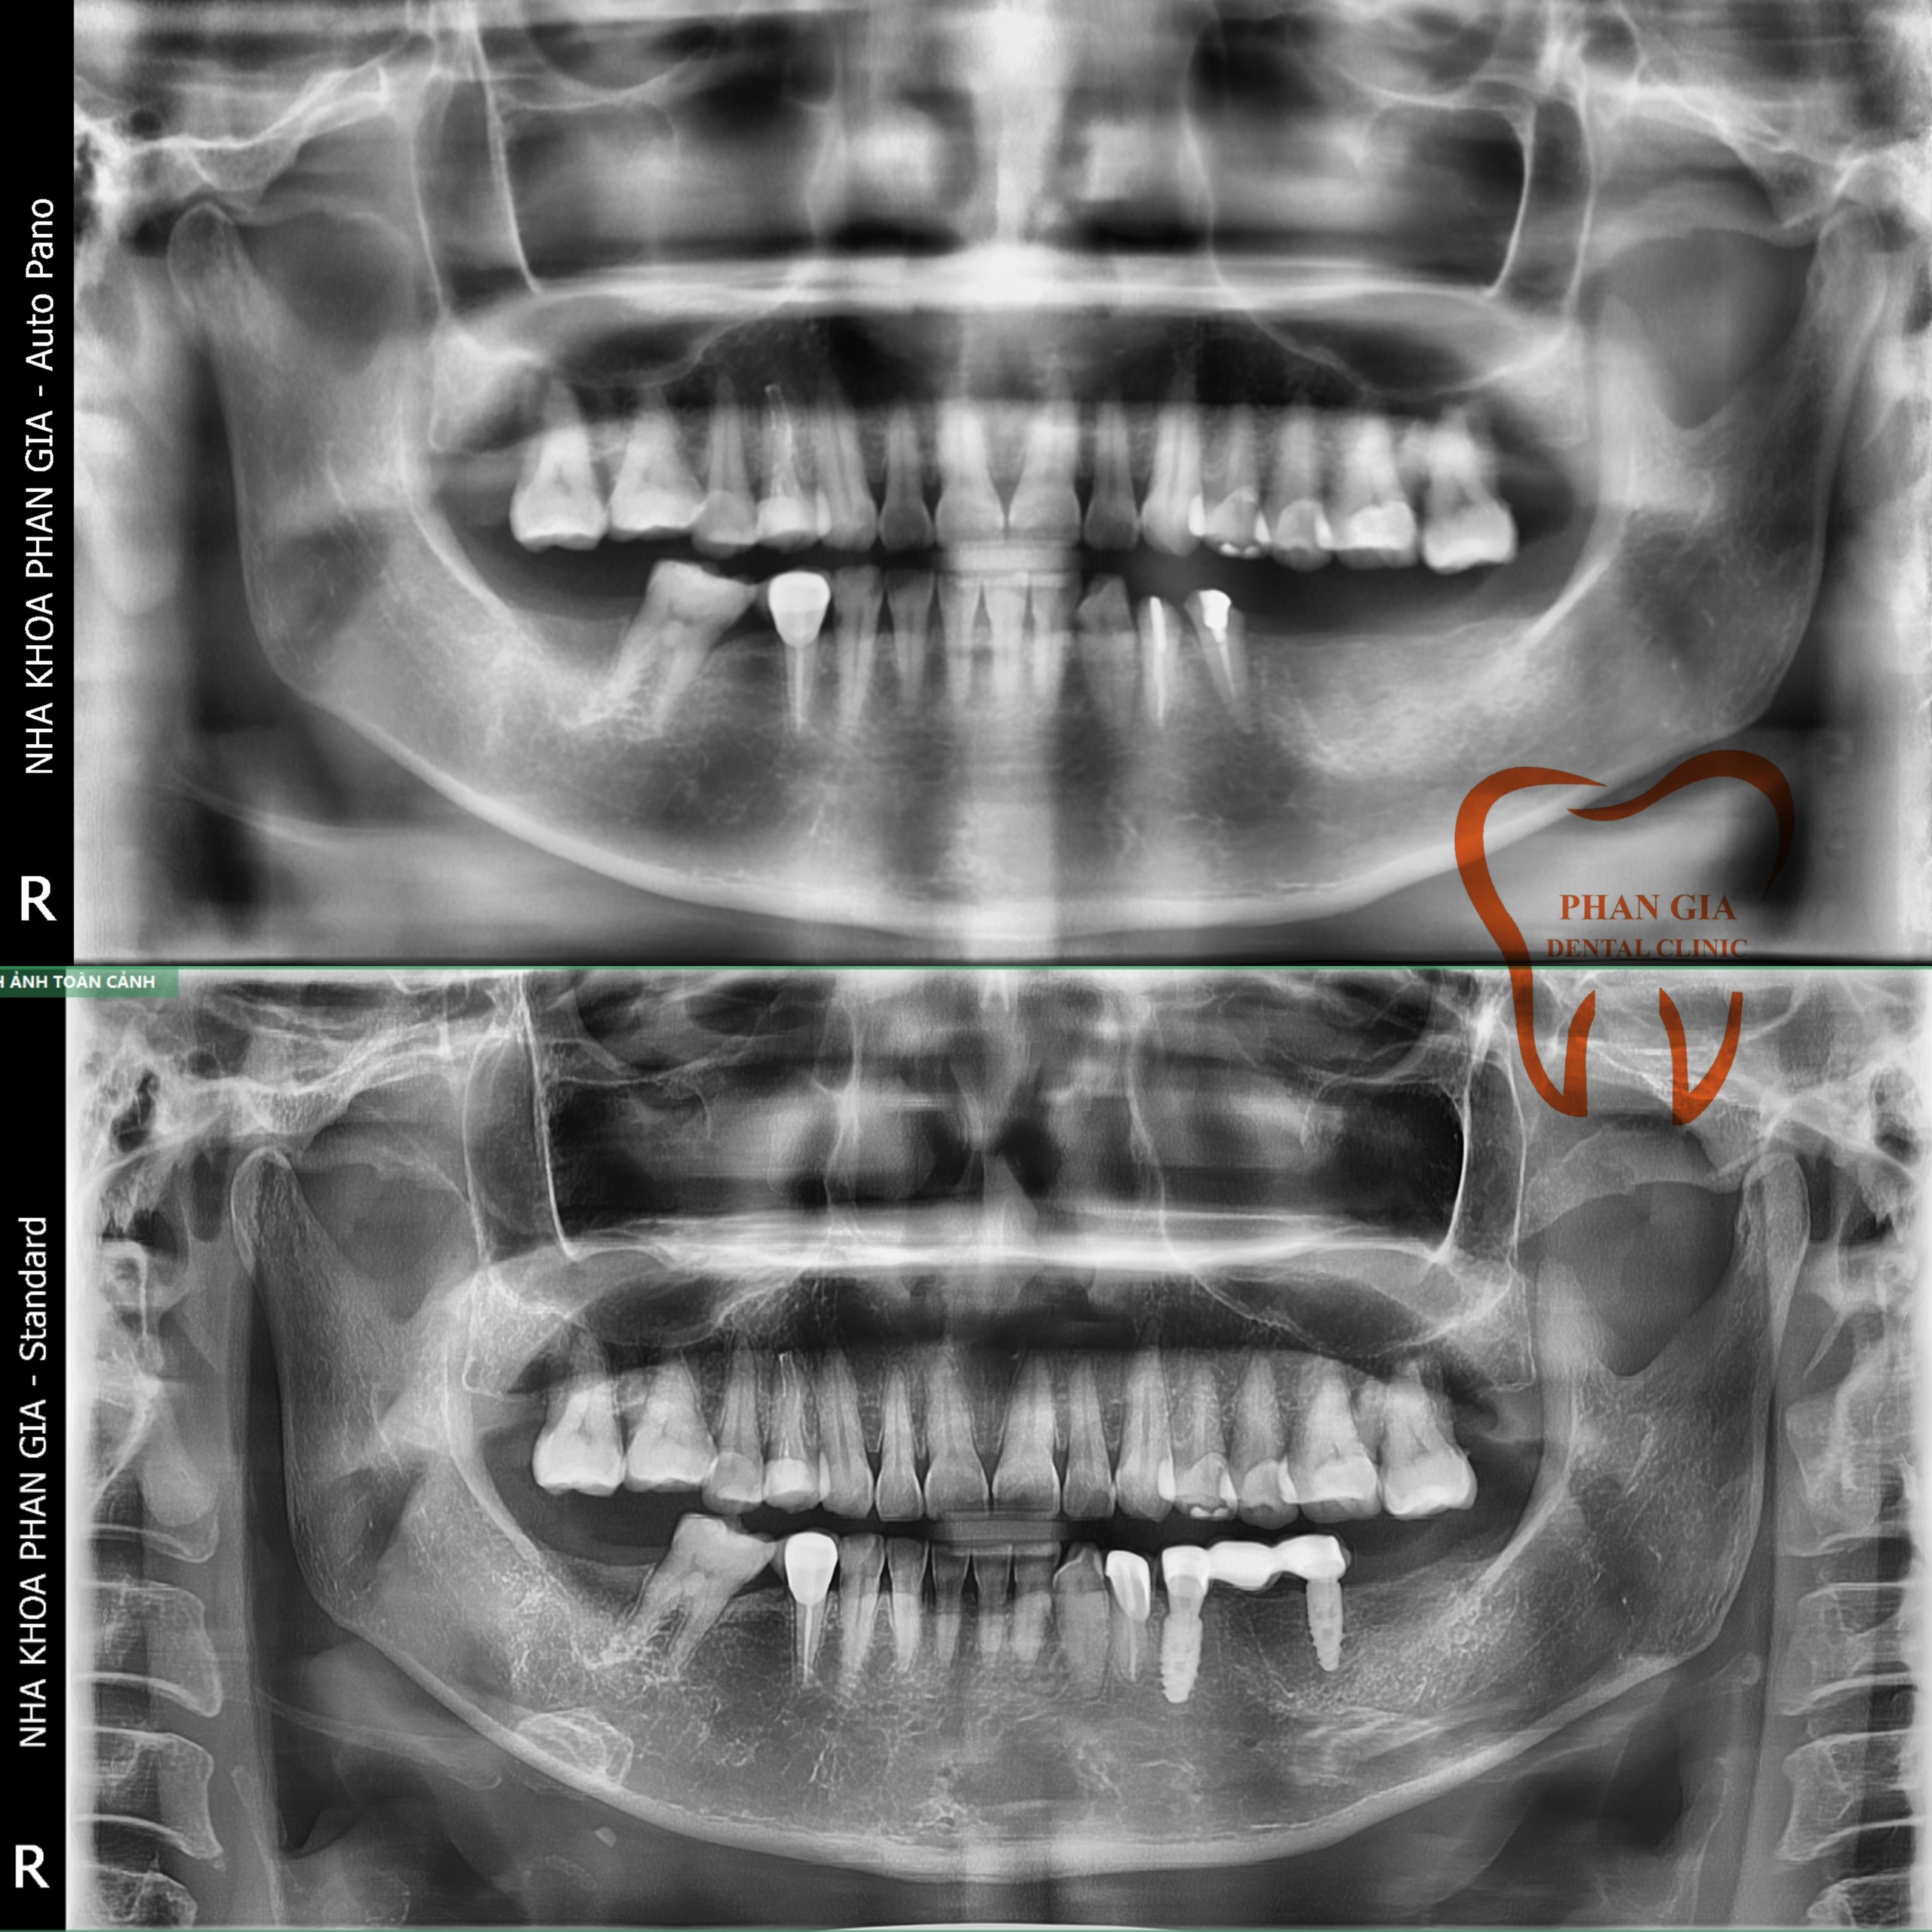

Khách hàng ngoại quốc tin tưởng và lựa chọn nha khoa PHAN GIA để tiến hành cấy ghép 2 trụ Implant và làm răng trên Implant thay thế cho răng cối đã mất. Sau thời gian hoàn thiện răng sứ trên implant khách hàng đã quay lại tái khám và cho feedback cực tốt cho nha khoa

Chú Q một case viêm nha chu vùng răng cối phân hàm 2 và 4 gây tụt nướu lộ chân răng, răng lung lay nhiều bắt buột phải nhổ bỏ . Khi nhổ đi dĩ nhiên không còn răng ăn nhai nữa, với tư tưởng không đeo hàn tháo lắp, muốn lựa chọn phương pháp phục hình cố định chú đã chốt đơn 6 trụ implant để làm lại răng đã mất phục hồi lại chức năng ăn nhai của răng hàm.

![]() |

Khách hàng Việt Hồng, trường hợp chị Hồng trước đây bị răng sâu vỡ lớn không thể giữ lại và 1 số R bị viêm nha chu, tụt nướu lộ chân R bắt buột phải nhổ. Bác sĩ tư vấn chị nên trồng lại các răng đã bị mất để có thể ăn nhai thoải mái trở lại do răng hàm trên của chị vẫn còn và chị vẫn còn trẻ.

Đặt hết niềm tin vào trình độ và tay nghề của đội ngũ Bác sĩ tại PHAN GIA chị quyết định lựa chịn cắm mỗi bên phân hàm 2 trụ implant rồi làm răng sứ lên đó để có răng ăn nhai trở lại.